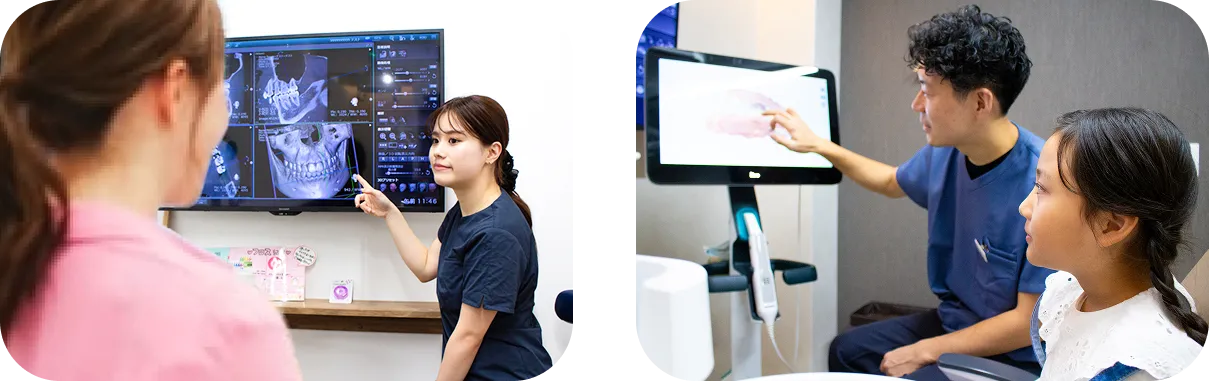

ベテランの歯科医師・

衛生士に相談できる

他院の歯科医師に矯正指導を行っているベテランのドクター・衛生士より、現状の歯並び・噛み合わせの問題点や、ご自身やお子様の矯正治療の必要性の有無についてお伝えします。

相談会で

将来の予測を立てられます

3Dシミュレーションで

- ✓あごの骨の形

- ✓歯・歯並びの状態

を知ることができます。

※年齢によってはスキャンが受けられない場合がございます。